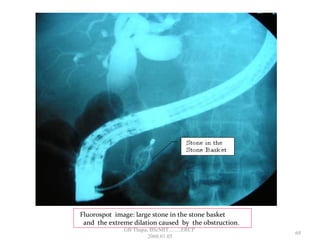

Fluorospot image: large stone in the stone basket

and the extreme dilation caused by the obstruction.

• 63.

• Once thestone is lodge in the basket, it is slowly pulled down the duct to the duodenum under the fluoroscopic guidance in order to insure that the stone is still lodged in the basket. • This process may be repeated if there are more stones left. • Smaller stones or stones that seem to be crushed by the stone basket may be removed again by using the balloon catheter. • Over 90% of CBD stones may be successfully removed by using a basket or Balloon & left to pass into the intestines where they will be eliminated in the stool. SPHINCTEROTOMY: Stone extraction 68 GB Thapa, BScMIT.........ERCP 2068.01.05